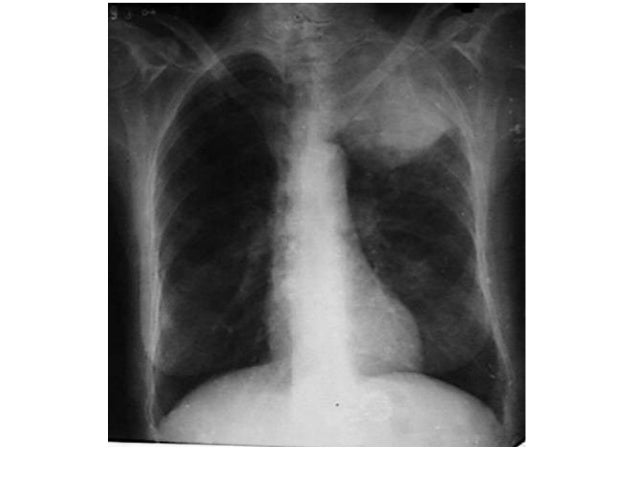

Cancer pulmonar .